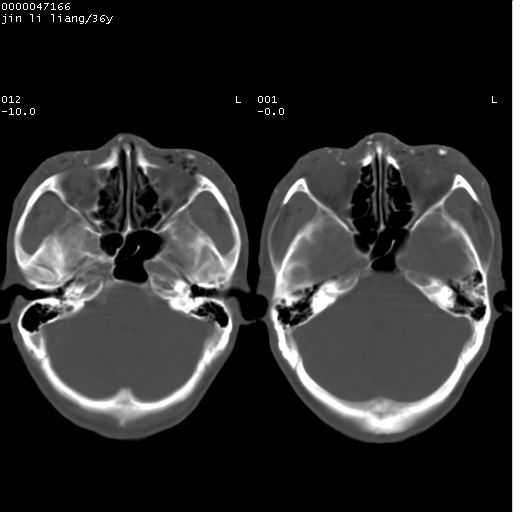

左眼球破裂,异物.

左眼球破裂,球内异物

左眼球内容物浑浊其内见气体影,头面部异物.

左眼球破裂并异物,眶周、额顶部头皮及软组织挫伤并异物

左眼球破裂积气并异物,眶周、额顶部头皮及软组织挫伤并异物!

迎面一炮,满脸开曝。额顶部头皮及软组织挫伤并异物,左眼球破裂积气并异物,典型的面目全非,惨不忍睹。

左眼球破裂积气并异物,眶周、额顶部头皮及软组织挫伤并异物,右侧眼环前内分异物

痛心,左眼啊!好在颅内还好。

1左侧眼球破裂并积气,球内、框内异物。

2额部顶部软组织伤。